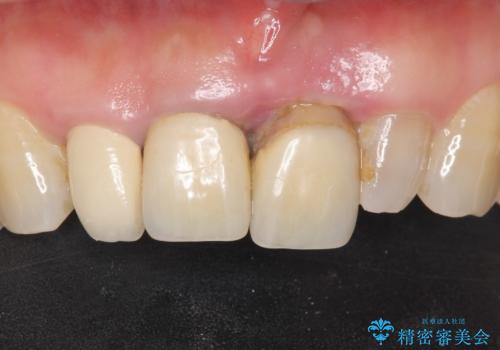

歯周病が重度であったため抜歯後の歯肉の陥凹が大きく、GBRや歯肉移植による歯周組織の再建をおすすめしましたが、ご希望されませんでした。

上の前歯の再根管治療もおすすめしましたが、必要性を感じないとのことで土台のやりかえだけをご希望されました。

- ¥1,010,000 (仮歯×9本、ファイバーコア×1本、ジルコニアクラウン スタンダード×9本)費用は治療当時の料金となります